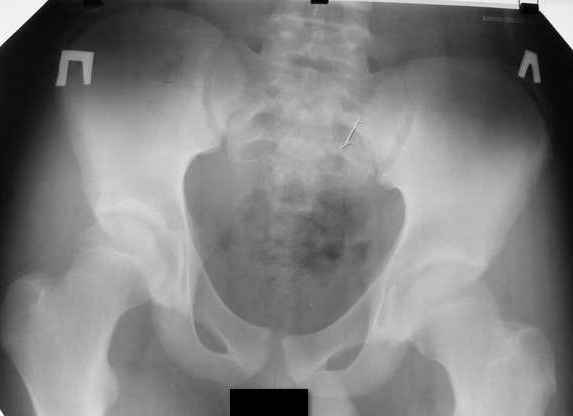

Please give standing X rays of legs include pelvis and ankles with comoensation of leg length. All best

Могу предложить только снимок таза.